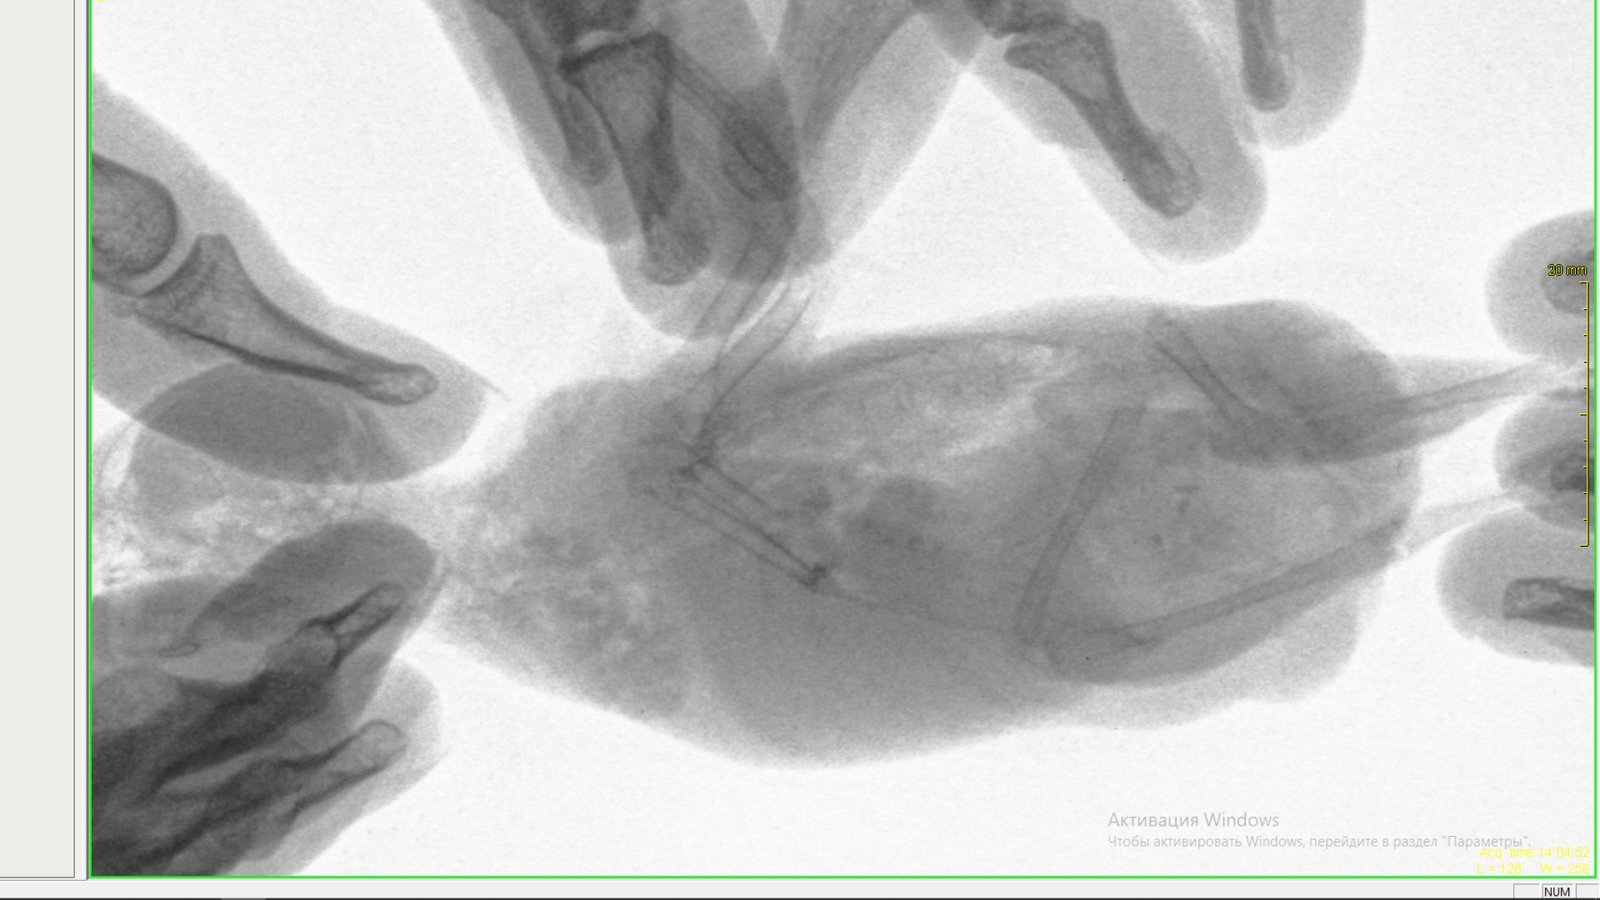

Zosia Опубликовано 11 августа, 2019 #11 Опубликовано 11 августа, 2019 Намочите перо НАД ХВОСТОМ, у его основания. И осмотрите зону копчиковой железы. Так же осмотрите зону основания шеи со стороны спины- нет ли там чего лишнего (как воротник, или локальное образование). На снимке семенники визуализируются, слегка опущены. А печень и кишечник- как каша... там идет воспалительный процесс. Копрограмму вам надо делать, интеерсуют жиры/жирные кислоты/мыла/лейкоциты/крахмалы Пока гепатовет, потмо возможно подключитмя урсосан, и я бы- в данном случае- гентамицин бы применяла (не люблю его, хуже чем энрофлоксацин). Доза 2,5 мг/кг, ищите капли глазные с гентамицином- их удобно прямо в клюв капать... Обязательно ампульный глюканат кальция иметь под рукой- как первый антигистаминный препарат. И нистатин (начнете его с 5 дня приема а/б)

Zosia Опубликовано 11 августа, 2019 #14 Опубликовано 11 августа, 2019 Автор,ну представьте- некое объемное образование нахожится в брюшной полости. Оно растет, сдавливает окружающие ткани, мешает им нормально функционировать. Наступает т.н. "патологическое состояние". И идет неинфекционный воспалительный процесс, с образованием спаек, тяжей, отложением фибрина... ну и на эту кашу если попадает условно=патогенная флора- то может и инфекционка пойти (но тогда достаточно быстрая ,хоть и неприятная,гибель). У меня есть видео вскрытий, где органокомплекс кишечника/печени/желудков представляет собой спекшийся ком- неразделимый... А один раз то,что было на рентгене (прижизненном) как каша- оказалось кровотечением в юрюшную полость (из-за деструкции тканей на фоне опухоли печени).